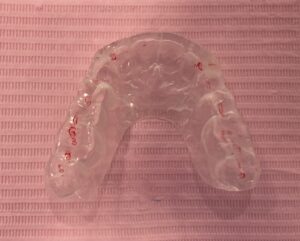

その位置を手掛かりにマウスピースのベースを作成します。

10日程のち、マウスピースは出来上がります。

こちらは装着時の体感検査です。

こちらのマウスピースは夜寝るときだけ入れていただきます。

翌週からマウスピースの調整を度々します。

顎が治っていく過程で、筋肉が緩みいろんな方向に動き出すためです。

そのため食いしばり歯ぎしりも消えます。

マウスピースの調整は、

このように全体が当たるようになり、前歯が横に動かす

ガイドになるまで続くのです。

調整の度、どんどん身体的、精神的症状はなくなるのです。